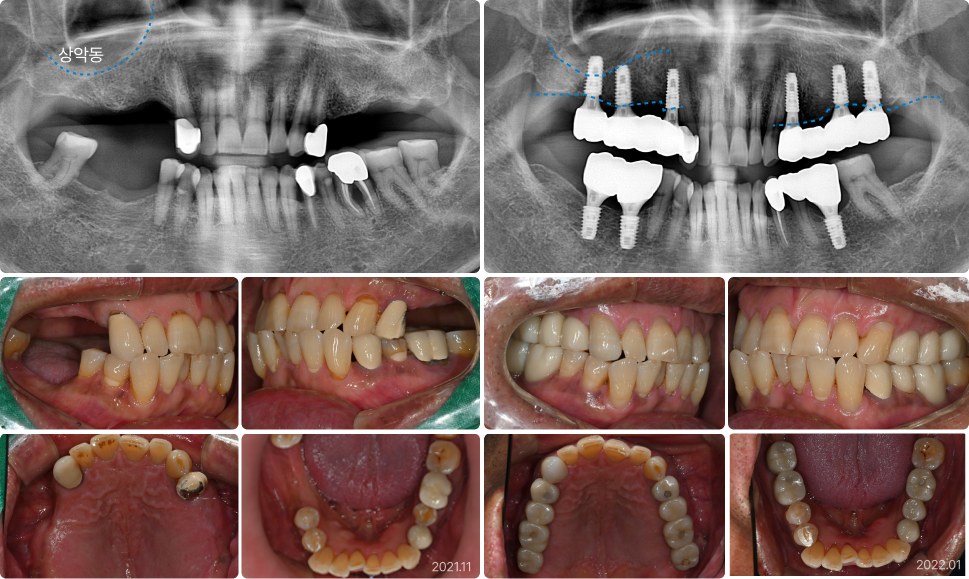

상악동 거상술 치료 사례

62세, 남

“위턱에 뼈가 하나도 없어서 임플란트를 못 한다고 했어요.”

치료 전

치료 후

• 상악동(빈 공간)이 커서 잇몸뼈가 1mm도 남지 않음

• PRF를 동반한 뼈이식, 상악동거상술로 안정적으로 잇몸뼈를

증가시킴